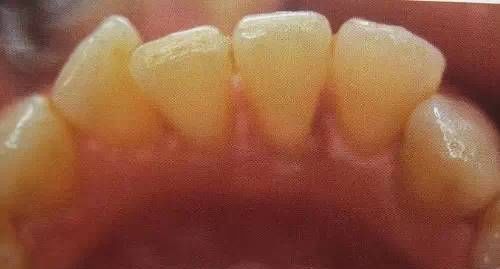

男性成年人喜欢喝茶、抽烟,造成牙齿表面色素沉着,很不美观

洗牙(洁治)后,洁白如一